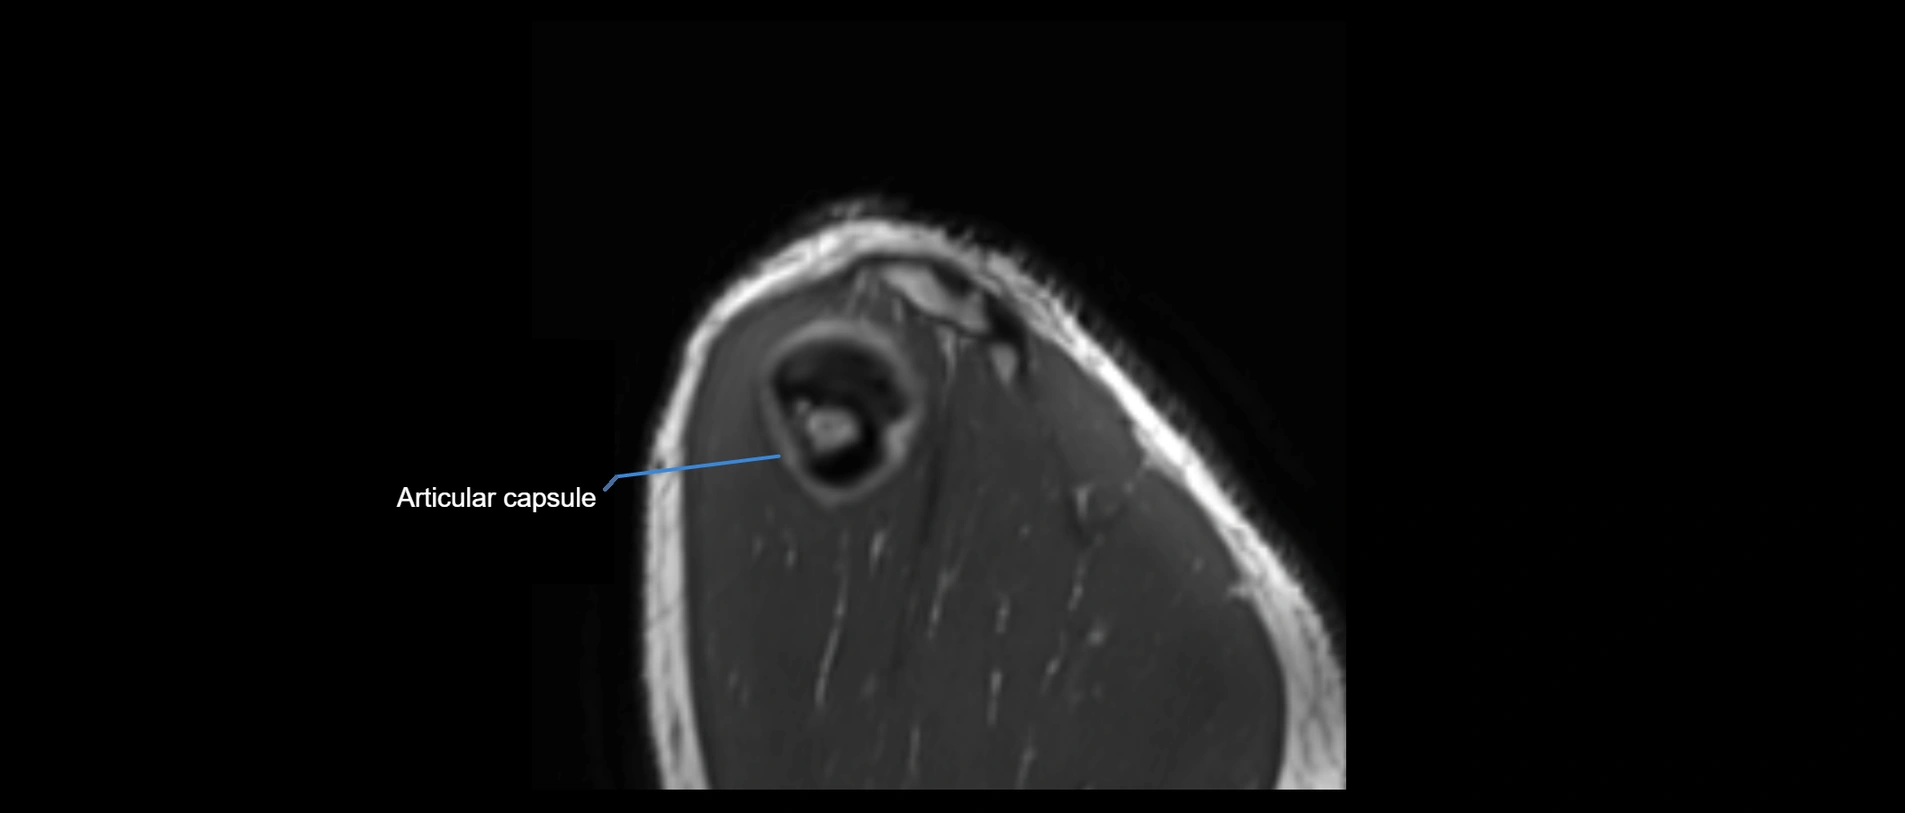

CT image

image

CT Appearance

Non-Contrast CT:

• Ligament: Not directly visualized due to small size and low density.

• Bony landmarks: Lateral clavicle and acromion clearly seen; cortical margins well defined.

• Pathology: Detects fractures, joint subluxation, osteophytes, and degenerative changes.

• Alignment assessment: Evaluates AC joint spacing and clavicular displacement.